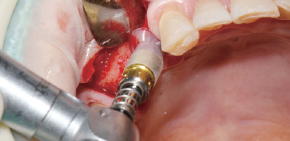

使用Ø3.5/4.0 Harvesting Drill的临床案例。

by Dr. Soohong Kim, DDS, Ph.D

确认种植体和采集部位后,一边注水一边以300rpm的速度钻孔。

根据不同的骨高度贴紧Silicone Shield,防止骨片遗失。

通过透明的Silicone Shield轻松地确认骨采集量。

在钻头上分离Silicone Shield和塞子后,将采集好的骨片放到Bone Dish中。

植入种植体后连接愈合基台,在缺损部位进行GBR。

*采集的第二部:钻孔4mm后,若塞子和Silicone Shield中装满了骨片,则将采集好的骨片放到Bone Dish后更换为7mm钻。